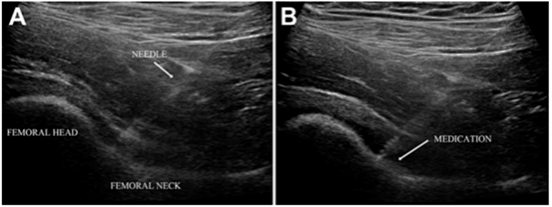

髋关节撞击综合征(FAI)的典型表现为腹股沟疼痛,但临床上亦不乏以髋后、腰骶和下肢等症状为主的非典型症状型FAI,这给临床诊断和治疗方式的选择带来了不小的挑战。为了解决这一问题,我科创新性地提出了超声引导下注射的方式用于诊断非典型症状型FAI。本研究共纳入了78名非典型症状型FAI患者,经过深入研究,我们发现超声引导下注射在诊断髋关节内病变的准确率高达91.7%,术后94.4%的患者临床结局评分超过了最小临床重要差异(MCID),91.7%的患者达到了可接受的症状状态(PASS)。基于上述研究结果,我们建议对于非典型症状型FAI的患者,可采用超声引导下注射的方式进行明确诊断。对于注射结果为阳性的患者,可考虑进一步采取手术治疗。这一诊断方法不仅提高了诊断的准确率,还为患者提供了更为精准的治疗方案。

Gao G, Fu Q, Wu R, Liu R, Cui L, Xu Y. Ultrasound and Ultrasound-Guided Hip Injection Have High Accuracy in the Diagnosis of Femoroacetabular Impingement With Atypical Symptoms. Arthroscopy. 2021 Jan;37(1):128-135.

超声引导下注射诊断非典型症状型FAI